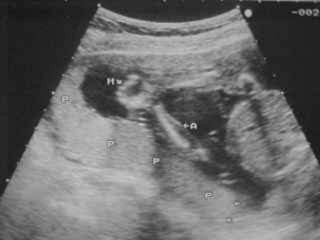

 MOVIMIENTOS RESPIRATORIOS FETALES

 MOVIMIENTOS CORPORALES GRUESOS

 TONO FETAL

 VOLUMEN LÍQUIDO AMNIÓTICO

 TNE (monitoreo)

ECO

PERFIL BIOFISICO FETAL